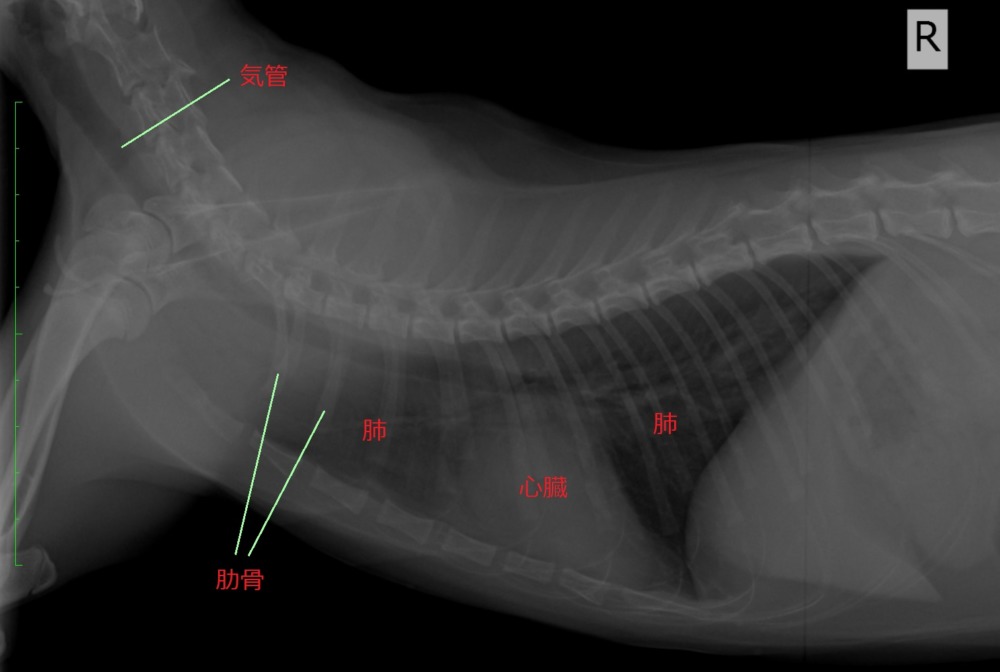

代表的な症例 ハヤシ犬猫病院

平成動物病院|当院の症例